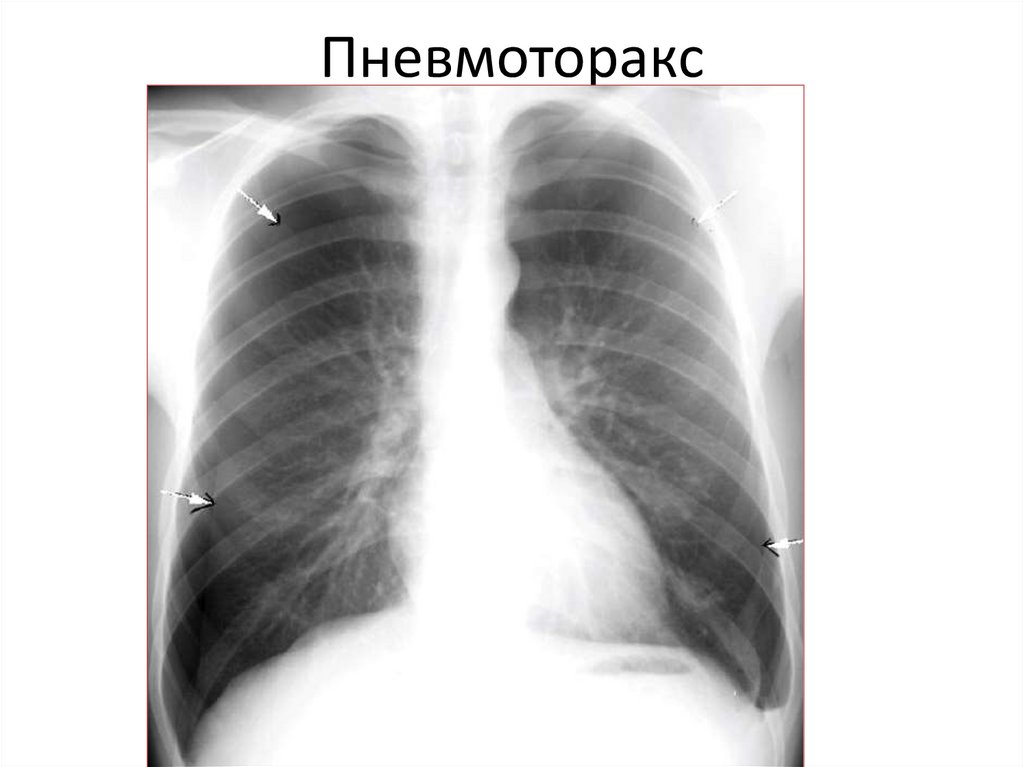

Пневмоторакс